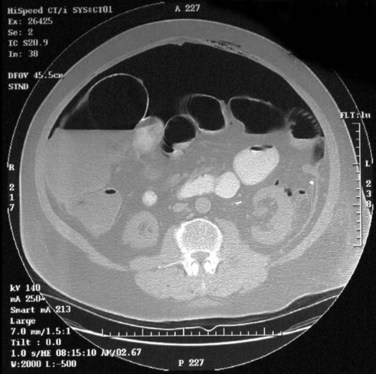

In addition to causing pain, cysts may compress the renal parenchyma or other adjacent organs, cause ureteral obstruction and obstructive uropathy, spontaneously bleed, cause hypertension, or become infected. Laparoscopic decortication or unroofing may be used to treat these cysts, which are typically simple in character (Fig. 55–22). Cysts with complex appearance, such as thickened septa, calcification, or enhancement (Bosniak class III-IV), may be explored and sampled laparoscopically to rule out renal cell carcinoma due to their increased risk of harboring malignancy (Cloix et al, 1996; Santiago et al, 1998). Options include cryoablation, enucleation, partial nephrectomy, or radical nephrectomy. If there is any question of cyst proximity to the collecting system, cystoscopy and placement of an open-ended ureteral catheter may be performed to ensure the integrity of the collecting system after cyst excision.

Figure 55–22 Axial CT scan in delayed phase after IV contrast administration, demonstrating peripelvic cysts in a patient who presented with left flank pain.